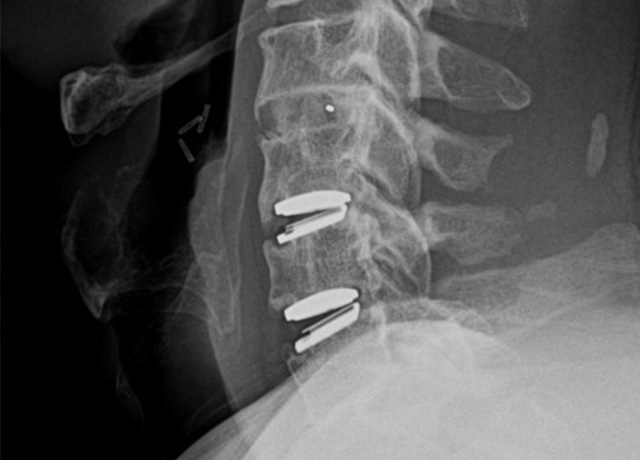

경추 유합술

(ACDF: Anterior Cervical Discectomy and Fusion)

경추 인공디스크 치환술

(Cervical Artificial Disc Replacement)

경우에 따라 두 수술을 동시에 시행할 수 있습니다.

각 병변에 가장 적합한 방식으로 치료 가능

불필요한 마디 고정을 피해 움직임을 최대한 보존

수술 한 번으로 여러 문제를 동시에 해결